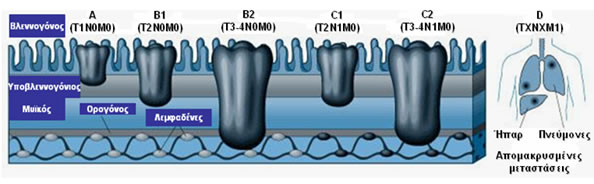

Τα σταδιοποιητικά συστήματα που έχουν χρησιμοποιηθεί για τον ορθοκολικό καρκίνο βασίζονται σε παρόμοιους προγνωστικούς παράγοντες: το βάθος διήθησης του πρωτοπαθούς όγκου, το βαθμό λεμφαδενικής προσβολής και την παρουσία απομακρυσμένων μεταστάσεων. Αυτό αρχικά περιγράφηκε από το σταδιοποιητικό σύστημα κατά Dukes και ακολούθως τροποποιήθηκε από τους Astler-Coller.

To τρέχον σταδιοποιητικό σύστημα βασίζεται στο στάδιο ΤΝΜ (Τumor- Βάθος διήθησης όγκου, Νodes- Λεμφαδενικές μεταστάσεις, Metastasis- Απομακρυσμένες μεταστάσεις), σύμφωνα με την Αμερικανική Ένωση Καρκίνου (American Joint Committee on Cancer Staging).

To σύστημα σταδιοποίησης ΤΝΜ και η αντιστοιχία με τα παλαιότερα συστήματα, συμπεριλαμβανομένης της πρόγνωσης των ασθενών (5ετής επιβίωση) αναφαίνονται στους Πίνακες 7 και 8 και στην Εικόνα 7.

Εικόνα 7.

Σταδιοποίηση καρκίνου παχέος εντέρου